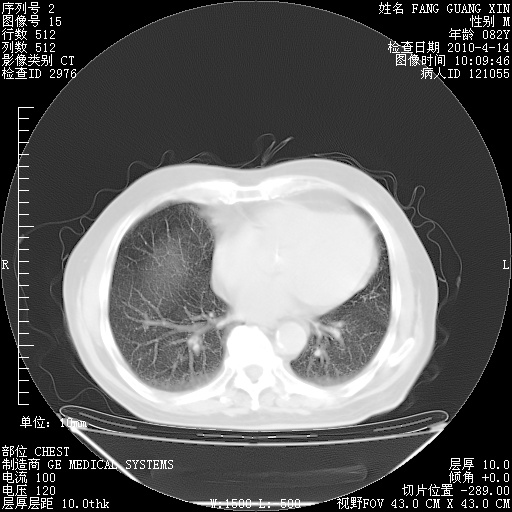

4月14日肺部CT

23.JPG

24.JPG

25.JPG

26.JPG

肺部CT平扫未见异常。